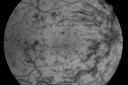

49-year-old woman has central retinal vein occlusion right eye with fluctuating vision and then recently her vision declined and she developed macular edema. I was worried about her angle and you were kind enough to do a peripheral iridotomy and I am dilating her today. Her vision is still poor. VISUAL ACUITY: OD 20/100. IOP: OD 20. There is a peripheral iridotomy, lens is clear, there is no rubeosis. EXTENDED OPHTHALMOSCOPY: OD: Vertical C/D ratio is 0.1. There is 2+ optic nerve edema, 3+ cystoid macular edema. The retinal veins are dilated in all 4 quadrants. The photos confirm clinical findings. Fluorescein angiogram shows some substantial delay in the venous circulation time with no non-profusion. IMPRESSION: 1. PERFUSED CENTRAL RETINAL VEIN OCCLUSION RIGHT EYE. 2. MACULAR EDEMA IN THE RIGHT EYE. DISCUSSION: I explained to the patient that with intravitreal Kenalog there is about an 80% chance of drying up the macula and improving the vision. There is a risk of cataract and glaucoma and a very low risk of infection. I injected the eye today without difficulty with the Kenalog.